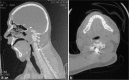

Background: Nonmissile penetrating spine injury (NMPSI) represents a small percent of spinal cord injuries (SCIs), estimated at 0.8% in Western countries. Regarding the causes, an NMPSI injury caused by a screwdriver is rare. This study reports a case of a retained double-headed screwdriver in a 37-year-old man who sustained a stab injury to the back of the neck, leaving the patient with a C4 Brown-Sequard syndrome (BSS). We discuss the intricacies of the surgical management of such cases with a literature review.

Conclusion: Screwdriver stabs causing cervical SCIs are extremely rare. This is the first case from Iraq where the assault device is retained in situ at the time of presentation. Such cases should be managed immediately to carefully withdraw the object under direct vision and prevent further neurological deterioration.